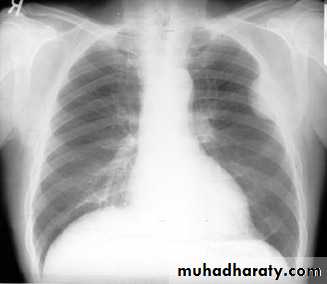

Pleural diseasespleural effusionpneumothorax hydro pneumothoraxpleural calcifications & thickeningpleural tumour